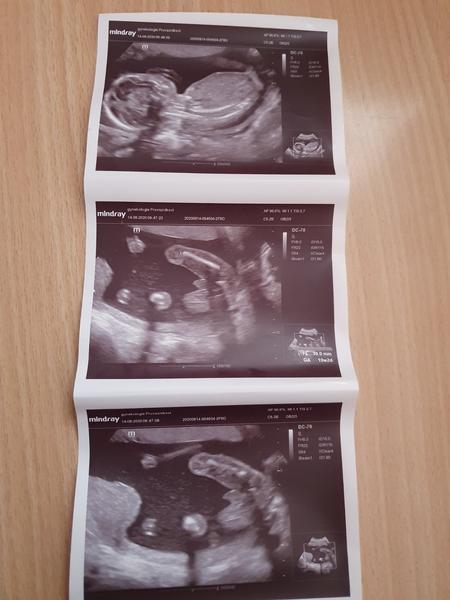

Ahoj maminky a budoucí maminky 😉 Prosím, poradila byste mi některá, co vidíte na fotce z ultrazvuku ve 20. týdnu za pohlaví? Určitě jste foteček viděly už mraky, proto vás žádám o radu...Nechci nikoho ovlivnit, proto svůj tip řeknu později 🙂 Děkuju moc!!!

@monca531 asi kluk no u nás kluk takto

@almidrob2539 tady to jde krasne vidět 😊 já si spis pořad vnitřně myslím ze bych mohla mít holčičku ale doktorka si byla opravdu jistá tak nic. Třeba za par let premluvim ještě chlapa na třetí 😂

@lemonade1111 řekla bych holku ☺️

@lemonade1111 rekla bych holcicka